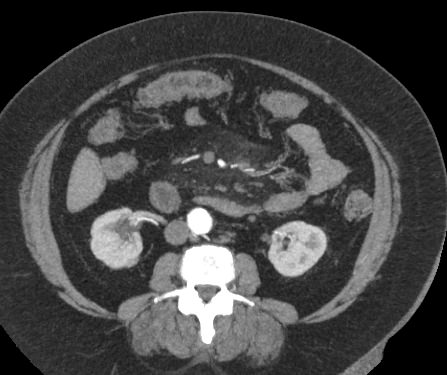

В брюшной полости и забрюшинном пространстве расположены группы лимфатических узлов, которые окружают внутренние органы (желудочные, печеночные, брыжеечные, чревные, подвздошные и др) и располагаются вдоль крупных кровеносных сосудов. Лимфоузлы относятся к периферическим органам иммунной системы человека и выполняют защитную функцию, являясь барьером для проникновения инфекций и задерживают распространение раковых клеток.

Патологические изменения регионарных лимфоузлов часто свидетельствуют о поражении того органа, от которого происходит лимфоотток. Это имеет важное значение для оценки распространенности онкологического процесса, выявления отдаленного метастатического поражения лимфатической системы, а также используется для определения тактики лечения. Кроме того, патология лимфатических узлов может говорить о развитии гемобластозов и лимфопролиферативных заболеваний крови.

Компьютерная томография позволяет детально визуализировать структуру лимфатических узлов, выявить ее неоднородность, гиперплазию, определить деформацию контуров, появление инфильтрации окружающих тканей с образованием пакетов и конгломератов лимфоузлов.

С целью повышения контрастности изображений, выявления патологических изменений в лимфоузлах дополнительно внутривенно вводится рентгеноконтрастное вещество на основе йода. Контраст накапливается в патологических очагах и под воздействием рентгеновских лучей обусловливает их яркое изображение на фоне неизмененной ткани. Контрастирование значительно повышает диагностическую ценность исследования и помогает выявлять многие серьезные заболевания на начальных этапах.

Что показывает КТ лимфоузлов с контрастом

• гиперплазия,

• неоднородность,

• пакеты, конгломераты лимфоузлов,

• изменения контуров,

• инфильтрация окружающих тканей,

• жировая ткань ворот узла,

• сдавление прилежащих органов, сосудов.

• уплотнение клетчатки, наличие жидкости.

• новообразование